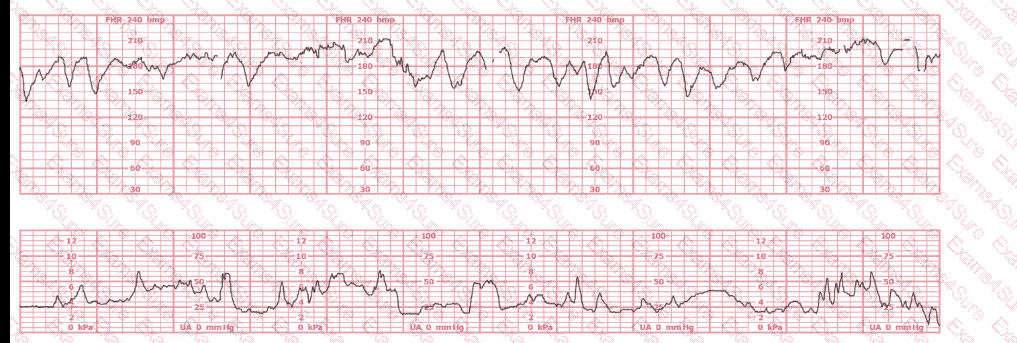

A woman in active labor at 8 cm experiences spontaneous rupture of membranes and acute bright red vaginal bleeding. The uterus is soft and nontender to palpation. The fetal monitor tracing has been normal and now shows tachycardia followed by bradycardia with minimal variability. The maternal blood pressure is 130/76 mm Hg, and the pulse is 86 beats per minute. The most likely cause of these findings is: